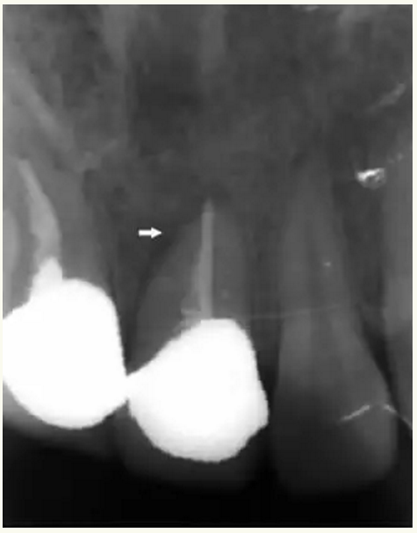

▲21牙根近中側(cè)位于根尖1/3和根中1/3交界處有牙周膜間隙略增寬

▲術(shù)后,手術(shù)切口處疤痕